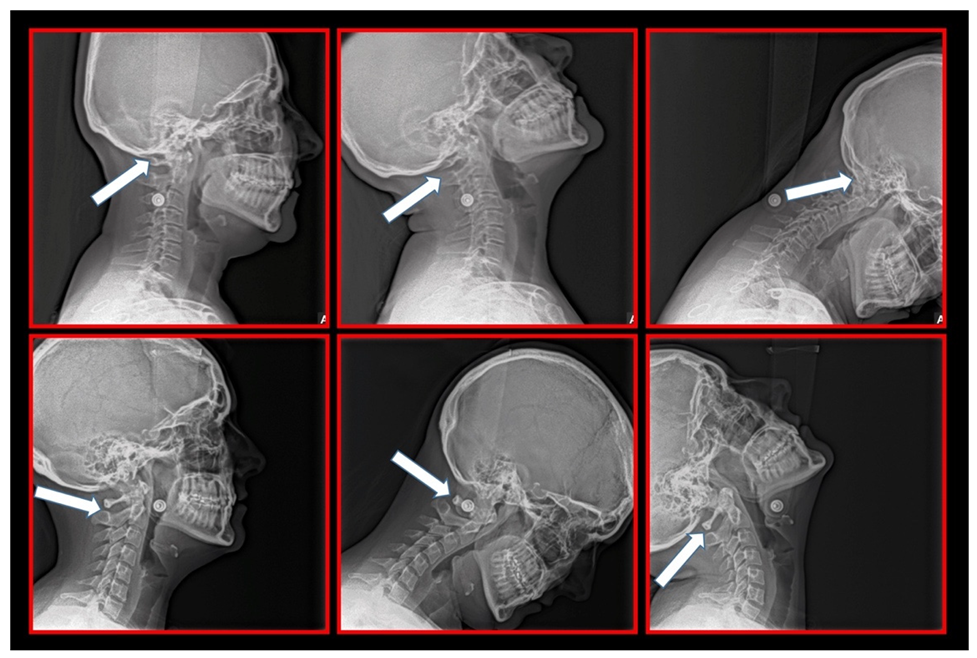

10.1. Neck X-ray

11.5. Axis and Atlas Derotation